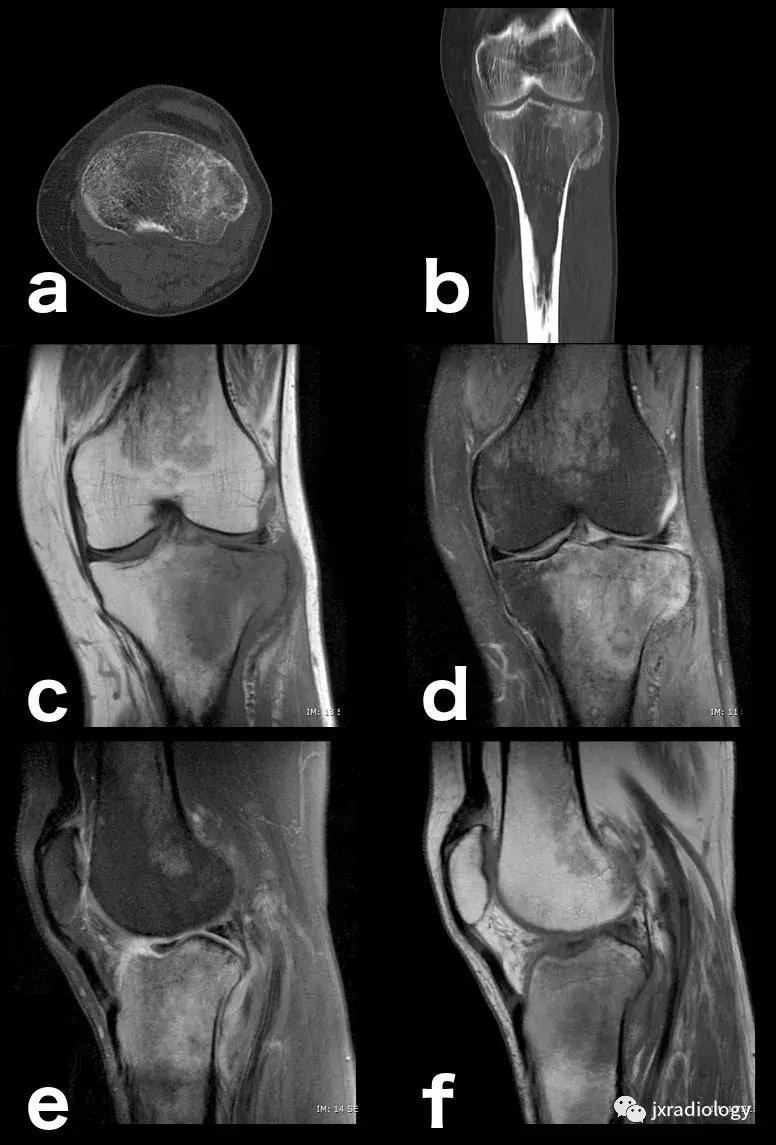

图14:创伤性骨水肿,肉眼可见的亚急性骨折:即使CT扫描(a,b)上的骨折线稍不明显,MRI上骨髓水肿也指出病变(c,d,e,f)。

图20:患有血红蛋白病的患者(例如镰状细胞性贫血),在这种情况下,容易发生继发于毛细血管阻塞的骨坏死。这种阻塞导致毛细血管静水压升高,造成水敏性序列中低信号骨梗死周围的高信号水肿。这是充血性骨髓水肿的一个例子(由于骨髓空间毛细血管床液体流出受损)。该患者还表现出广泛的红骨髓转化,如T1-WI中的骨髓信号所示(远低于周围脂肪组织并略高于肌肉组织)和DP-FS-WI(未完全饱和,保持略高信号)( a:冠状面DP-FS-WI; b:冠状面T1-WI; c:轴向T1-WI; d:矢状面DP-FS-WI)。

图22:骨肉瘤(a,b:冠状和轴向PD-FS-WI):肿瘤性水肿继发于骨小梁破坏引起的直接毛细血管损伤,并伴有血管内液体释放和出血。区分周围水肿和肿瘤侵袭可能是困难的。

图23:骨巨细胞瘤(PD-FS-WI):也存在肿瘤性骨髓水肿。

图24:骨样骨瘤:在这些良性肿瘤中,水肿可以继发于前列腺素E2引起的炎症反应(a,b:横断位和冠状CT扫描; c,d:横断位T1-WI和冠状位PD-FS-WI)。